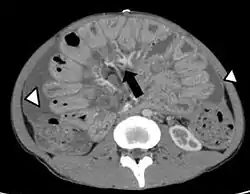

La peritonitis puede definirse como un proceso inflamatorio que afecta al peritoneo y es secundario a una infección bacteriana o irritación química. El peritoneo es la membrana serosa que cubre por dentro la pared del abdomen y la mayoría de los órganos situados en su interior. La peritonitis puede ser localizada o generalizada, aguda o crónica. La causa más frecuente es una infección causada por la perforación de una víscera hueca, por ejemplo apendicitis aguda perforada, perforación gástrica o diverticulitis con perforación. La peritonitis aguda suelen manifestarse por dolor abdominal, náuseas, vómitos, fiebre, hipotensión y taquicardia. Puede provocar graves complicaciones, entre ellas fallo orgánico múltiple y muerte.[1]